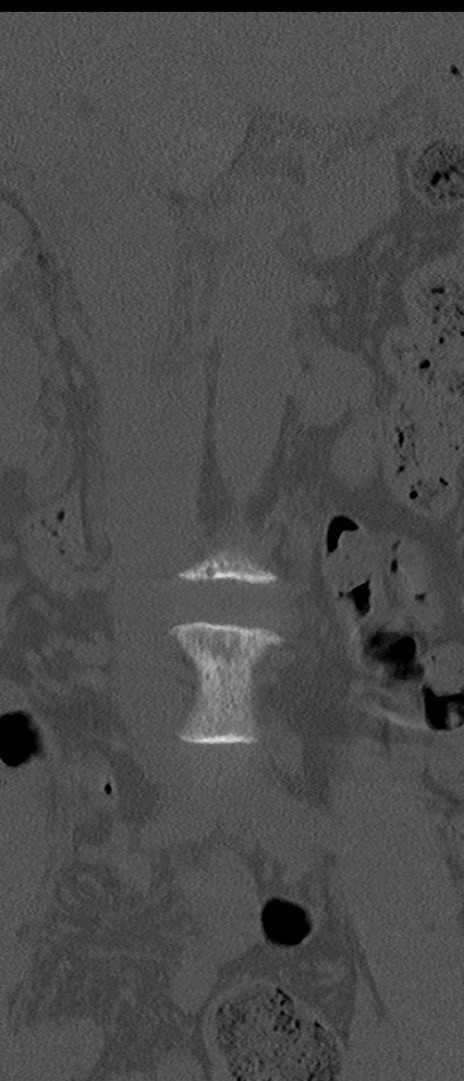

腰椎CT